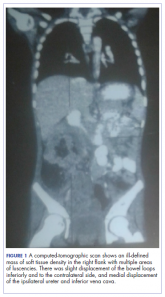

Carcinoma of the colon in a child